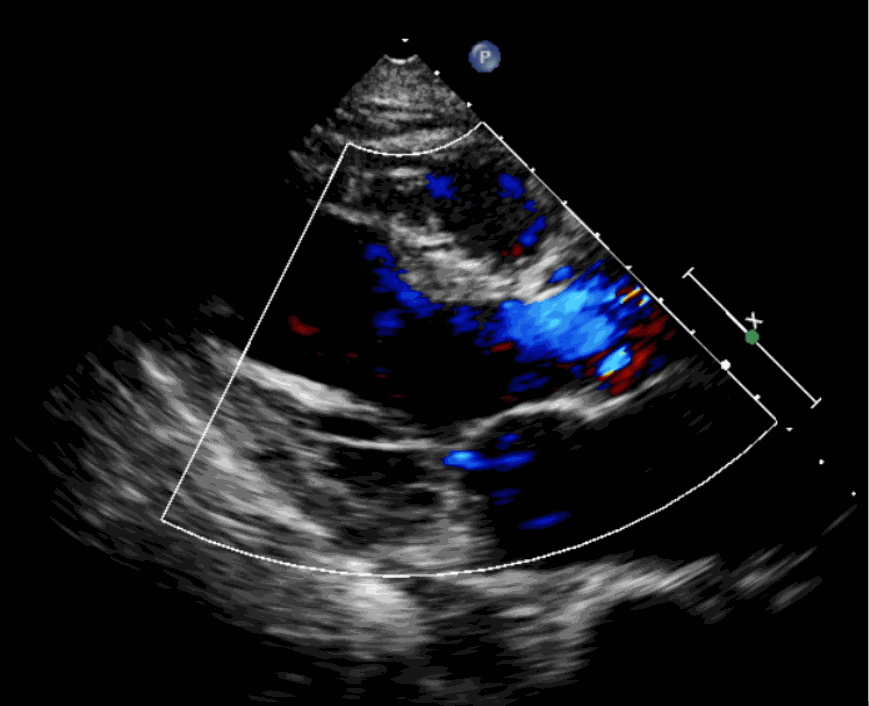

該例患者為62歲,女性,因“間歇性心悸、胸悶、氣短、胸痛1年,加重1周”之主訴入院。入院診斷:主動脈瓣重度關閉不全,二尖瓣、三尖瓣輕度關閉不全,心功能III級;冠狀動脈粥樣硬化性心臟病。行心臟超聲心動圖提示“主動脈瓣重度關閉不全;瓣口水平以下左室下壁、后下壁搏幅減低;EF值 0.30,左房、左室大、右房大小正常高限;二尖瓣、三尖瓣關閉不全;輕度肺動脈高壓(收縮壓42mmHg);主動脈硬化;左室收縮功能重度減低。經心血管外科劉洋、楊劍教授、麻醉科陳敏教授及超聲科孟欣教授等專家團隊綜合評估,判定患者為外科手術高危患者。

術前超聲影像圖